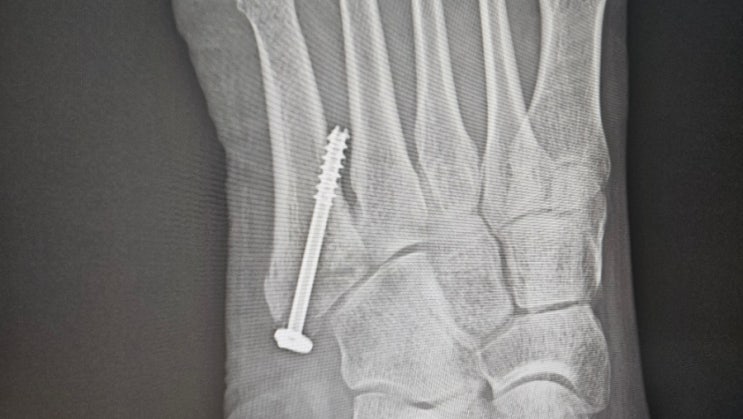

중족골 핀제거수술 1일차

5월20일 중족골수술을 하고 거의6개월이 지났다 시간이 약인 골절... (골절수술후기도 있습니다) 핀박은부...

중족골골절 수술 9주차 상태

5월20일 중족골골절 수술 7월7일까지도 수술 봉합부위 절개자국이 일자로 그대로 선명하게 보이고 각질도 ...

중족골골절 수술 7주차 골절50일째 목발 안녕

2024년7월2일 골절 50일째 5월13일 골절 5월20일 월 중족골골절 수술 후 엘병원 입원 5월24일 금 퇴원 낚시...